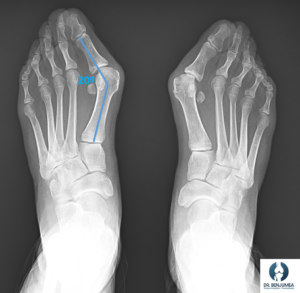

Para planificar la cirugía es necesario realizar unas radiografías de ambos pies en carga donde podamos valorar cómo se comporta realmente el pie cuando este soporta nuestro peso. Estas radiografías nos indicarán qué tipo de correcciones debemos realizar y si puede estar indicada una técnica y otra.